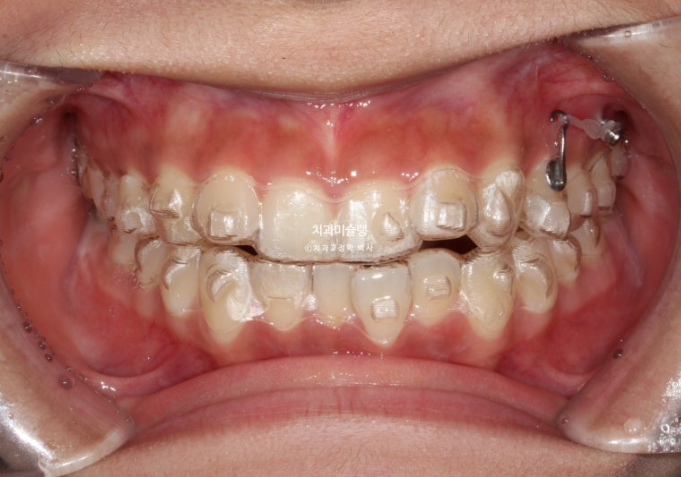

24년 여름방학을 이용해서 교정상담을 온 유학생 환자분입니다.

측절치의 개방교합, 아래 앞니 덧니 등 보입니다.

우측 교합관계는 1급에 가깝지만

좌측 교합관계는 2급입니다.

사랑니를 빼고 사랑니 공간으로 어금니를 후방이동 시켜 교합관계를 맞추고 덧니 해소할 공간을 얻기로 합니다.

돌출이나 뻗침은 없어서 비발치로 진행하는 것 입니다.

인비절라인 컴프레헨시브 프로그램으로 교정치료에 들어갔습니다.